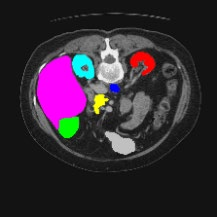

Transformers have made remarkable progress towards modeling long-range dependencies within the medical image analysis domain. However, current transformer-based models suffer from several disadvantages: (1) existing methods fail to capture the important features of the images due to the naive tokenization scheme; (2) the models suffer from information loss because they only consider single-scale feature representations; and (3) the segmentation label maps generated by the models are not accurate enough without considering rich semantic contexts and anatomical textures. In this work, we present CASTformer, a novel type of generative adversarial transformers, for 2D medical image segmentation. First, we take advantage of the pyramid structure to construct multi-scale representations and handle multi-scale variations. We then design a novel class-aware transformer module to better learn the discriminative regions of objects with semantic structures. Lastly, we utilize an adversarial training strategy that boosts segmentation accuracy and correspondingly allows a transformer-based discriminator to capture high-level semantically correlated contents and low-level anatomical features. Our experiments demonstrate that CASTformer dramatically outperforms previous state-of-the-art transformer-based approaches on three benchmarks, obtaining 2.54%-5.88% absolute improvements in Dice over previous models. Further qualitative experiments provide a more detailed picture of the model's inner workings, shed light on the challenges in improved transparency, and demonstrate that transfer learning can greatly improve performance and reduce the size of medical image datasets in training, making CASTformer a strong starting point for downstream medical image analysis tasks.